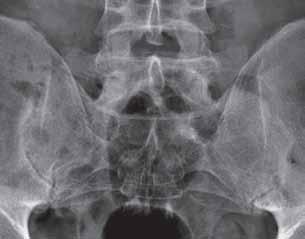

Rycina 2.9.

Zwężenie szpary stawu biodrowego u dwóch różnych osób. Po stronie lewej koncentryczne, z obecnością geod i nadżerek powierzchni stawowych – obraz wskazuje na chorobę zapalną (możliwość współistnienia jałowej martwicy aseptycznej głowy kości udowej).

Po stronie prawej zwężenie w części górnej, z obecnością osteofitozy wieńcowej i przebudowy sklerotycznej wewnętrznej części szyjki kości udowej, przy braku obecności nadżerek powierzchni stawowych – obraz wskazuje na chorobę zwyrodnieniową.